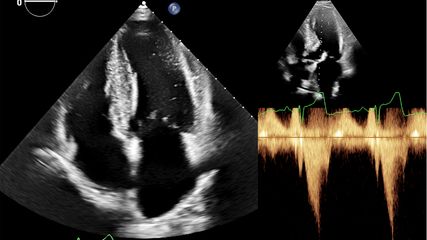

Charwat-Resl erläuterte, dassdieTransthyretin-Amyloidosedurch die Ablagerung von Amyloidfibrillen im Myokard entsteht, wenn das Transportprotein Transthyretin zerfällt. Dies kann auf eine genetische Disposition zurückgehen (hereditär), kann jedoch auch sporadisch aus unbekannten Gründen auftreten (Wildtyp). Charwat-Resl betont allerdings, dass das Vorhandensein von Amyloid noch keine Amyloidose definiert, sondern dafüreine klinische Diagnose erforderlich ist. Durch die Ablagerungen kommt es zu einer progredienten infiltrativen Kardiomyopathie, die sich in Myokardhypertrophie sowie einer Störung der diastolischen und später auch der systolischen Linksventrikelfunktion äußert. Klinisch führt das zu Herzinsuffizienz mit Belastungsdyspnoe, Beinödemen und rascher Erschöpfbarkeit. Noch vor wenigen Jahren war die Prognose schlecht. Seit einigen Jahren stehenAmyloid-spezifische Therapien zur Verfügung, mit denen sich kausal in den Krankheitsverlauf eingreifen lässt. Dazu eignen sich unterschiedliche Strategien, die teilweise bereits mit zugelassenen Substanzen verfolgt oder derzeit nur beforscht werden. Eine dieser Strategien ist die Stabilisierung von Transthyretin mit dem Ziel, die Dissoziation des TTR in Monomere zu verhindern.